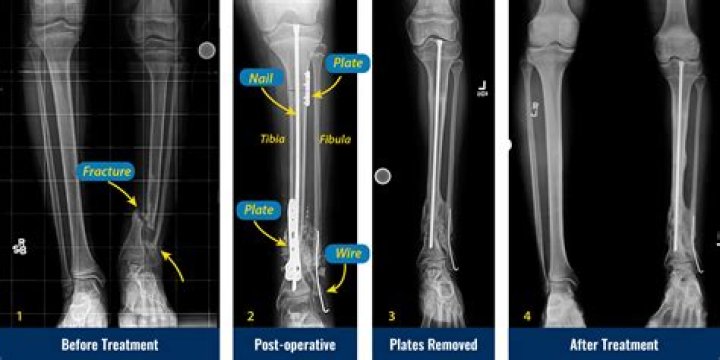

Treatment. Tibia fractures are treated based on the location and alignment of the fracture as well as the age of the child. Most tibia fractures in children can be treated in a cast or a boot. In some cases, the child may need to be sedated to set the bone before placing the cast.

Treatment options for tibial fractures can include:

1. Immobilization. A splint, sling, or cast that helps keep the bones in place while it gets better.

2. Traction. Traction is a method of stretching your leg so that it can stay straight.

3. Surgery. Surgery may be needed to fix a broken tibia.